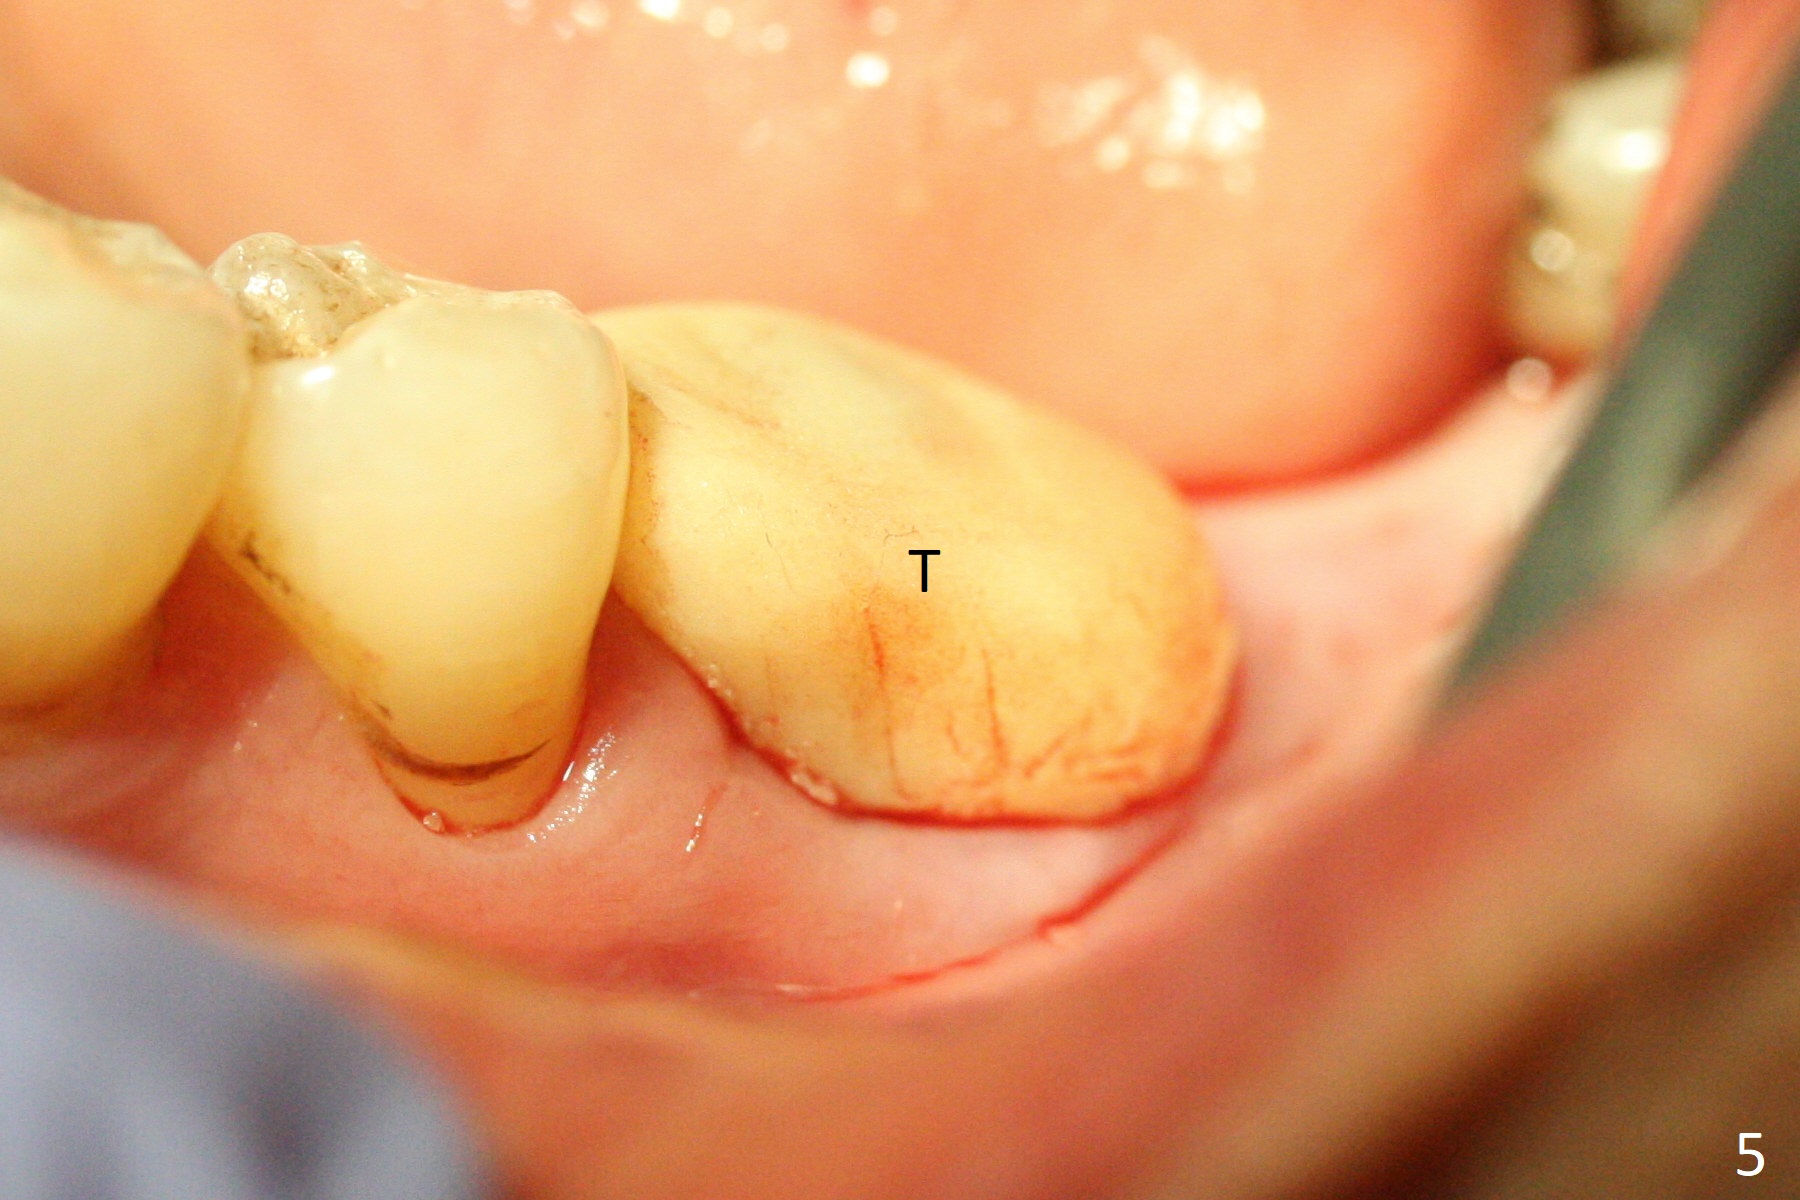

A 68-year-old man returns for extraction of the tooth #19 with distal root periodontal-endodontic lesion (Fig.1 *). After discussion, he agrees immediate implant. A 4.5x11.5 mm implant will be placed in the mesial socket (Fig.2 (red line: superior border of Inferior Alveolar Canal)); the plateau level with the septal crest (<). Osteotomy is initiated in the lingual slope of the mesial socket; the depth is controlled with stopper (Fig.3 S). The implant is placed at the level as expected (Fig.4 <) with insertion torque ~30 Ncm; after placement of 5.7x4(3) mm abutment and Osteogen plug (P) in the apical half of the distal socket, bone graft (G) is placed in the remaining socket gaps, mainly distal and buccal. An immediate provisional is fabricated to keep the graft in place (Fig.5 T). The graft may be lost if the gingival margin recedes in healing. Periodontal dressing is applied for additional security (Fig.6). There is no postop paresthesia. The upper border of the Inferior Alveolar Canal in Fig.3,4 seems to be high. In fact it may be a branch of the Inferior Alveolar Canal (Fig.7 yellow line, as compared to Fig.4). With all of measures taken (including periodontal dressing), the distal bone graft (Fig.8 *) is ~ 2 mm coronal to the crestal bone (red line) 6 months postop. The temporary crown is perforated. The gingival cuff is erythematous. A 6.8x5 mm healing abutment is installed. When the patient returns for impression, a 4.5x5.5(3) mm abutment is fully seated (Fig.9 <). The distal height increases by 4 mm because of immediate implant (support). The mesial papilla remains normal in height and shape immediate post cementation (Fig.10), as related to the mesial socket implant placement without mesial crestal bone loss. The mesial and distal crestal height is maintained 13 months post cementation (Fig.11, weight lifter).